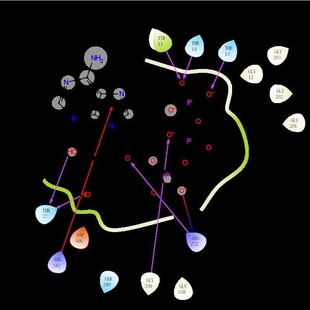

清北博士團(tuán)隊(duì)虛擬篩選 蛋白對(duì)接 網(wǎng)路藥理學(xué) 動(dòng)力學(xué)模擬 分子對(duì)接

清北博士團(tuán)隊(duì)虛擬篩選 蛋白對(duì)接 網(wǎng)路藥理學(xué) 動(dòng)力學(xué)模擬 分子對(duì)接由淘寶網(wǎng)為您挑選。折后價(jià)格4.95元,已有0人購買,選自掌柜鵬飛科技 。

?小紅書推薦?清北博士團(tuán)隊(duì)虛擬篩選 網(wǎng)路藥理學(xué) 動(dòng)力學(xué)模擬 分子對(duì)接 蛋白對(duì)接,所屬其它設(shè)計(jì)服務(wù)分類,由淘寶網(wǎng)挑選推薦!小紅書抖音網(wǎng)紅同款!哪里有賣清北博士團(tuán)隊(duì)虛擬篩選 網(wǎng)路藥理學(xué) 動(dòng)力學(xué)模擬 分子對(duì)接 蛋白對(duì)接和多少錢質(zhì)量怎么樣?。 照片精修服務(wù) ps設(shè)計(jì) 圖片處理 藝術(shù)照婚紗照精修 相冊(cè)設(shè)計(jì)服務(wù) 代寫施工組織設(shè)計(jì)土建橋梁園林深基坑高支模市政工程施工方案編寫 專業(yè)做標(biāo)書投標(biāo)物業(yè)采購餐飲服務(wù)技術(shù)標(biāo)施工組織設(shè)計(jì)方案競標(biāo)南寧 訂 名片設(shè)計(jì)烘焙店專用廣告宣傳卡片美容院開業(yè)家政服務(wù)小卡電子版 專業(yè)做標(biāo)書投標(biāo)采購服務(wù)技術(shù)標(biāo)施工組織設(shè)計(jì)方案競標(biāo)代做呼和浩特 函數(shù)設(shè)計(jì)圖表定制 excel表格制作數(shù)據(jù)處理分析vba代做宏編程序公式 C4D軟件2025 服務(wù)OC渲染器材質(zhì)球預(yù)設(shè)包插件 2024建模設(shè)計(jì)遠(yuǎn)程安裝 平面廣告海報(bào)設(shè)計(jì)制作封面主圖詳情頁宣傳單畫冊(cè)ps做圖修圖片p圖 2020設(shè)計(jì)軟件 遠(yuǎn)程安裝 2022 2021 2024 pr2025 稿定設(shè)計(jì)會(huì)員個(gè)人商用稿定設(shè)計(jì)會(huì)員搞定 稿定設(shè)計(jì)vip會(huì)員周月年卡 logo設(shè)計(jì)原創(chuàng)商標(biāo)品牌企業(yè)公司店標(biāo)志餐飲vi卡通字體圖標(biāo)名片門頭 下載字體 以圖找字體 做圖改字 包 字體安裝 代找字體 查找字體 字體識(shí)別查找ps字體AI字體pr代找字體下載字體查找中英文日韓 2022 Zemax OpticStudio光學(xué)設(shè)計(jì)軟件遠(yuǎn)程安裝 服務(wù)2019 2024 2023 設(shè)計(jì)辦公禮品個(gè)性 化定制服務(wù) 幸福我做主96小店 我